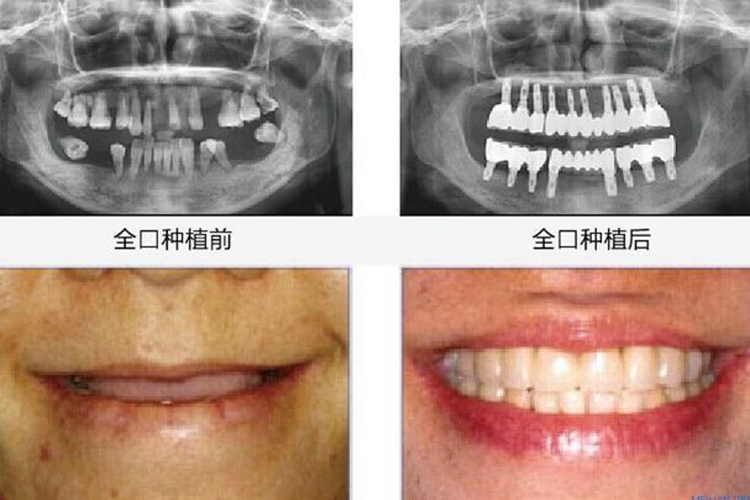

全口种植牙在使用时非常接近自然牙,而且大多比自然牙洁白、整齐。

种植牙的外形逼真,稳定性好,体积小,更舒适卫生,而且美观度可得到很大提升,特别是咀嚼功能恢复极好,种植牙无需磨损邻牙、咀嚼功能强大、生命力更长久。